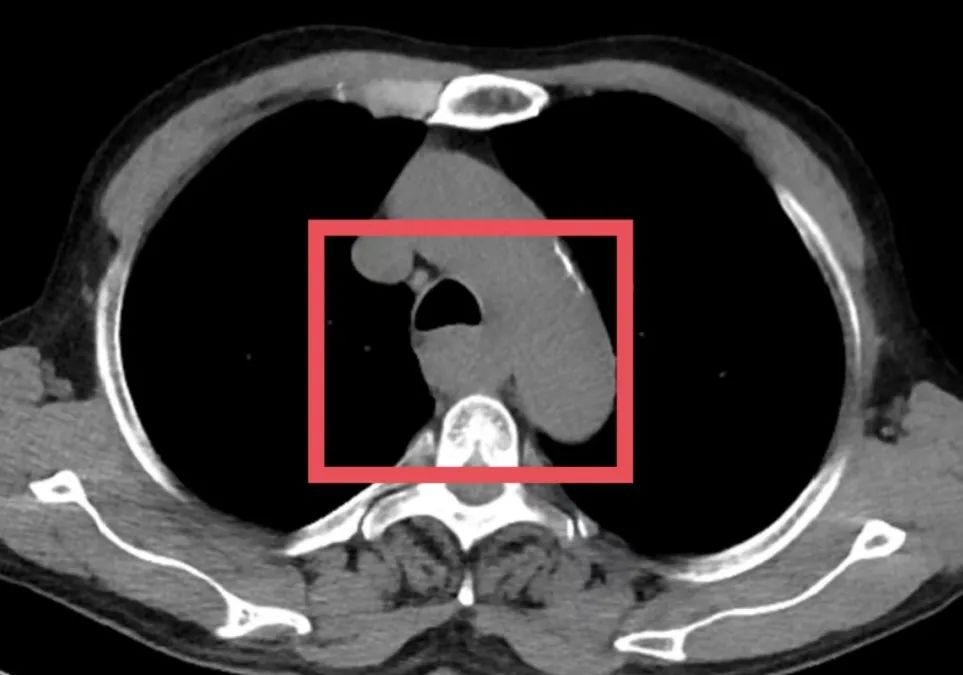

▲患者术前影像学检查

为了争取更大的根治机会,胸外科朱震主任医师为苏先生量身定制定了一套治疗方案——“免疫联合化疗”的新辅助治疗方案,先“软化”肿瘤、减少侵犯,再择期手术。治疗期间,苏先生接受了PD-1单抗与铂类+紫杉醇联合化疗。随着治疗推进,患者主诉症状显著缓解。2025年7月复查CT提示病灶缩小、边界清晰、与周围结构粘连减少,手术时机成熟。

▲患者术前、术后影像对比